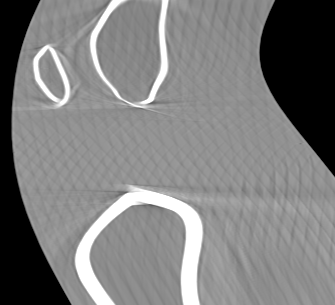

Involuntary subject motion is the main source of artifacts in weight-bearing cone-beam CT of the knee. To achieve image quality for clinical diagnosis, the motion needs to be compensated. We propose to use inertial measurement units (IMUs) attached to the leg for motion estimation. We perform a simulation study using real motion recorded with an optical tracking system. Three IMU-based correction approaches are evaluated, namely rigid motion correction, non-rigid 2D projection deformation and non-rigid 3D dynamic reconstruction. We present an initialization process based on the system geometry. With an IMU noise simulation, we investigate the applicability of the proposed methods in real applications. All proposed IMU-based approaches correct motion at least as good as a state-of-the-art marker-based approach. The structural similarity index and the root mean squared error between motion-free and motion corrected volumes are improved by 24-35% and 78-85%, respectively, compared with the uncorrected case. The noise analysis shows that the noise levels of commercially available IMUs need to be improved by a factor of $10^5$ which is currently only achieved by specialized hardware not robust enough for the application. The presented study confirms the feasibility of this novel approach and defines improvements necessary for a real application.